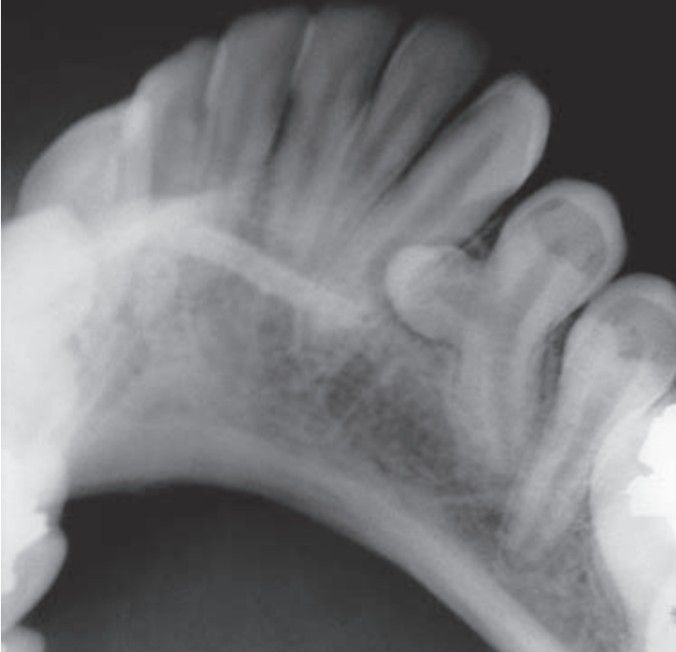

Gemination

Gemination is the fusion of two teeth from a single enamel organ.The typical result is partial cleavage, with the appearance of two crowns that share the same root canal.